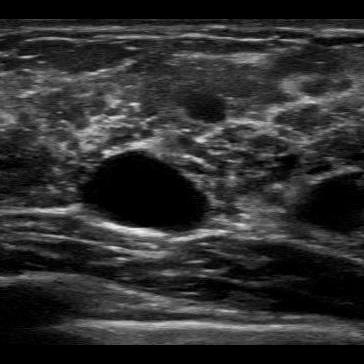

To evaluate the performance in terms of OOD detection, three different OOD test data sets were used: MNIST (test set), CorruptPOCUS and CCA. The MNIST test set consists of 10 000 images of handwritten digits [14]. The CorruptPOCUS and CCA data sets were chosen to resemble realistic OOD data, such as ultrasound images containing artefacts. The CorruptPOCUS data set resembles POCUS images of poor quality and was generated by distorting the POCUS test set by adding dark areas, blur and noise. The CCA data set contains 84 ultrasound images capturing the common carotid artery [15], i.e., non-breast US images. An example of a real POCUS image of poor quality as well as examples of the three OOD data sets can be seen in Fig. 2.